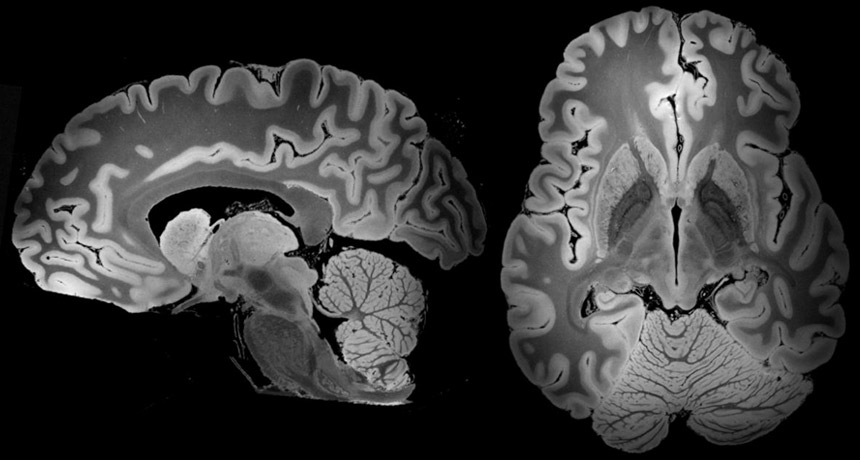

MRI Captures The Most Detailed View Yet Of A Whole Human Brain

www.sciencenews.org

www.sciencenews.org

mri brains scan smallest tumor indians hyderabad iit taken cocaine reveals detection brainscan